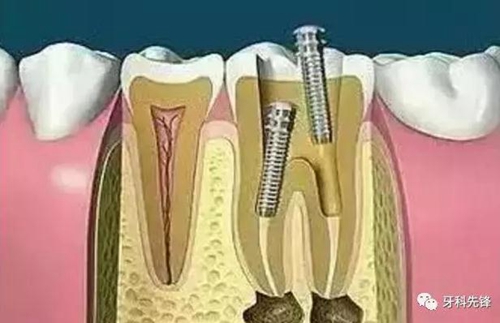

7、根管打樁

因牙體缺損過多,導(dǎo)致牙的強(qiáng)度(承受力量的性能)大幅度下降,不能很好地承受咀嚼力量。打樁的目的是增加牙根及牙冠的強(qiáng)度,增加患牙的穩(wěn)固。